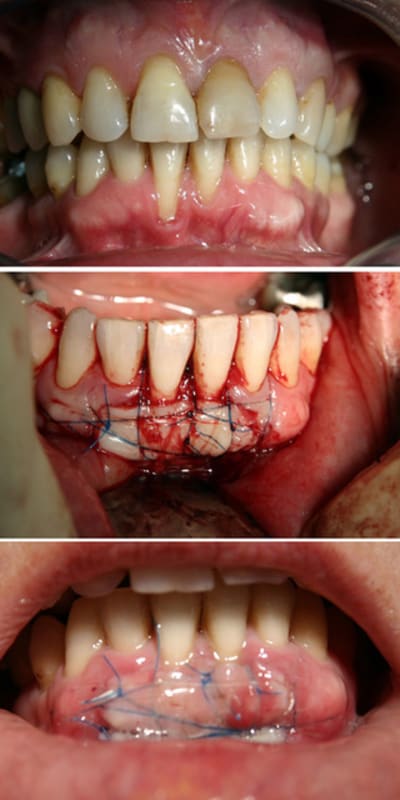

j' aile les greffes, c' est grave docteur?

sympas tes greffes, Carole, tu places un pansement type coepack en post-opératoire?

ça dépends du temps (météo) et du feeling.....sur le cas que tu vois complet de a à z, il n' y en a pas eu, car top stabilité et uniuement de l' os en dessous

Par contre, sur la deuxième, avec les racines de 41-31, j' en ai mis....pour un max de stabilité et de protection contre les micro mouvements qui font bcp de dégat en regard des zones couvrant les racines (qui sont les plus suceptibles).Et toi?

t'utilise du fil non resorbable pour ce type de greffe ?

si, j' ai tjrs utilisé du resorbable...sauf pour cette dernière...pourquoi???? pour essayer!

verdict:

*le flop : difficile à tendre lors de la suture

*le top: hygiene, compatibilité avec coe pack, faile à deposer car glisse très bien dans les chairs.

ma conclusion: à ne pas mettre en oeuvre pour les premières fois! ;)

oui, j' étais très speed quand j' ai posté! je vous envoie la cicat à 15 j demain ou samedi...

comme promis, voici la cicat à J 15 ....la suite quand je l' aurais photographié!!! (notez la prise de risque, car je ne montre pas "un cas qui a bien marché" mais bien mon dernier cas....si ça capote, c' est un rateau live que je prends dans ma frimousse!!!!)

bah pour l'instant, ta frimousse est exempte d'une incrustation de rateau....bravo, c'est joli (le boulot et la frimousse )